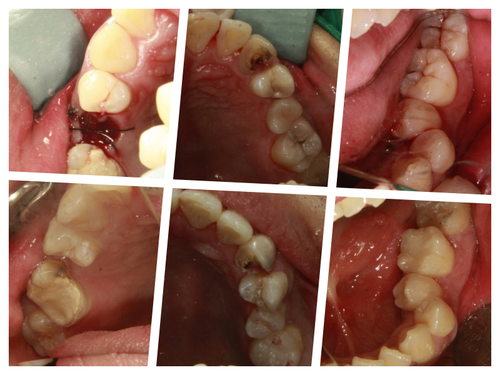

발치가 필요한 치아 치료는 미루시고 나머치 충치 치료를 진행.. 인레이 인상뜰 때 주무시면서 구토까지 하셨다.. 옆에서 이 모든과정을 도와준 우리 직원이 글을 쓰면서 다시 한 번 고맙다..

그래도 무사히 계획된 치료를 다 받고 치료 후 사진도 수면 상태에서 겨우 찍어서 환자분께 보여드렸다..